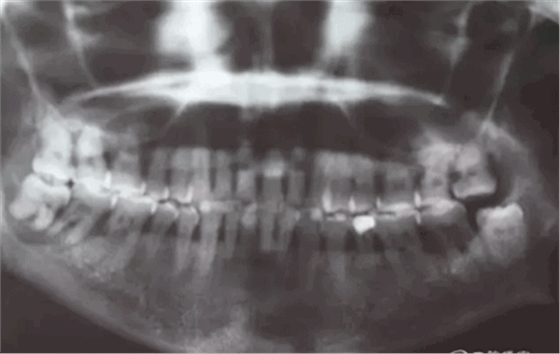

患者,白xx,女,40歲。主訴:右側(cè)下后牙牙探針齦反復(fù)腫痛,不能吃東西數(shù)月。專科檢查:48松動(dòng)Ⅲ,47松動(dòng)Ⅱ,牙周探針:48牙周袋均8mm,47遠(yuǎn)中牙周袋8mm,x全景片檢查:48牙槽骨弧形吸收至根尖區(qū),陰影較大。47遠(yuǎn)中牙槽骨吸收至遠(yuǎn)中根尖部,近中牙槽骨部分角形吸收。診斷:拔除48,試保留47.同期實(shí)行47牙周刮治術(shù)。患者同意治療方案,簽知情同意書。

圖2.局部的放大影像情況。48骨質(zhì)吸收至下頜管邊緣,陰影范圍廣,拔除48后牙槽窩處理要小心。